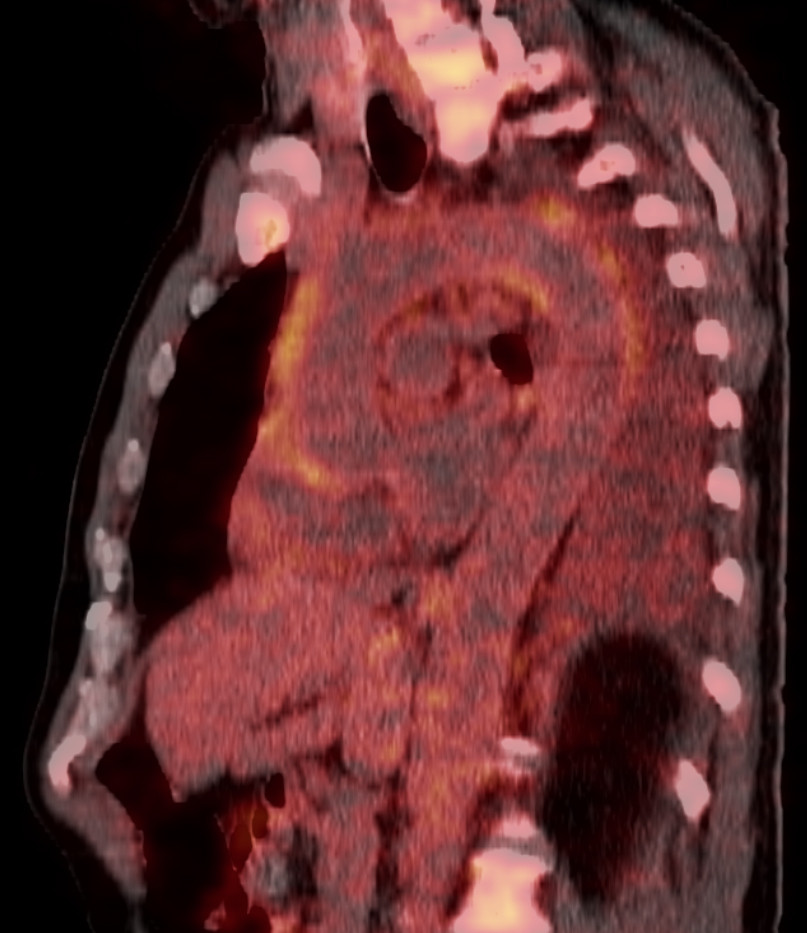

PET-CT-undersøkelse med ¹⁸F-fluordeoksyglukose (¹⁸F-FDG) utført ved innleggelsen viste økt opptak av ¹⁸F-fluordeoksyglukose i torakalaorta, buekaravganger og perikard (figur 1).

Det var også økt opptak av ¹⁸F-fluordeoksyglukose i benmarg og lymfeknuter, som ble vurdert å være reaktive forandringer. I tillegg ble det funnet et infiltrat i venstre lunges underlapp og pleuravæske (figur 2).